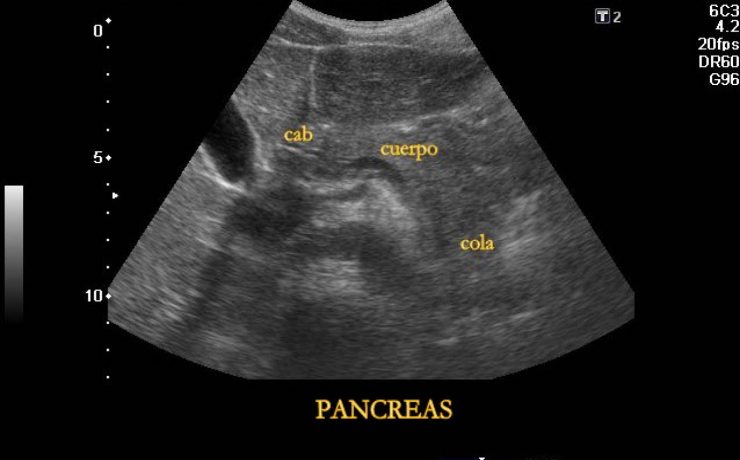

Más del 95% de las enfermedades biliares, son debidas a colelitiasis. En Estados Unidos su costo anual asciende a 8 millones de dólares, el 40% de los mayores de 40 años tiene colelitiasis y10 a 30% presentaran síntomas. 11% de la población adulta de E.U.A. Tiene cálculos biliares y esta